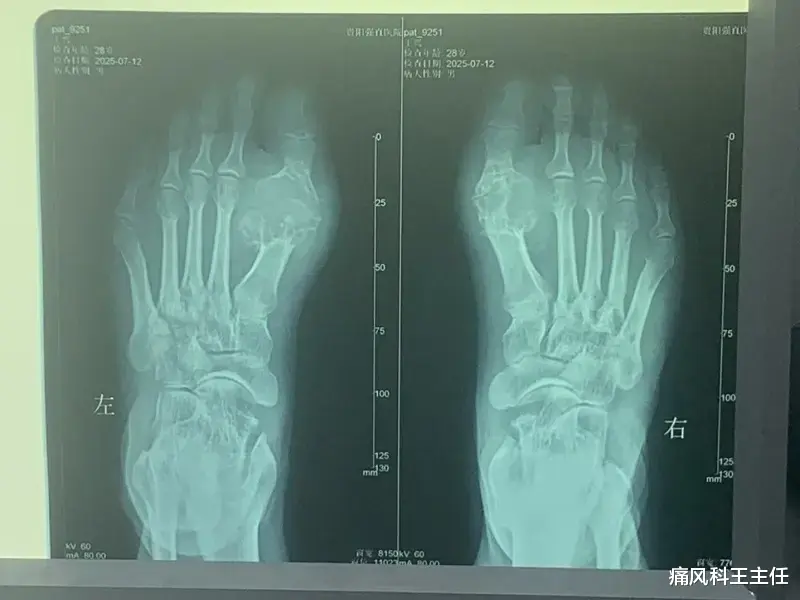

二、尿酸盐结晶:关节里的"玻璃渣"

微创清理技术:针刀镜可清除关节腔92.3%以上尿酸盐沉积,术后需联合专科技术促进肌腱韧带等残留尿酸盐脱落,消除炎症,促进创口的愈合。

长期管理要点:血尿酸需稳定<360μmol/L(有痛风石者<300μmol/L)才能溶解结晶。伴有皮下痛风石者,需持续达标5年以上方可完全清除。